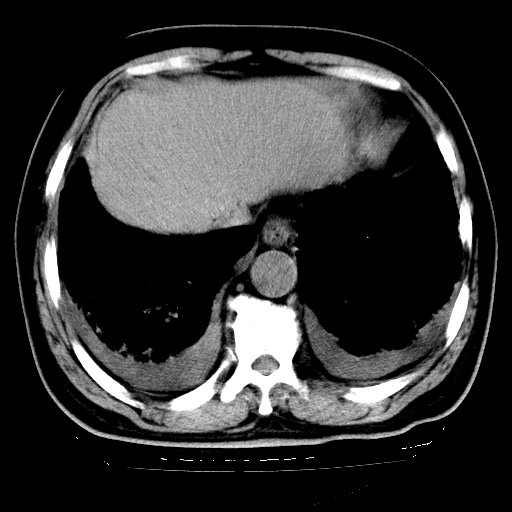

男,68岁,咳嗽、胸闷、发烧三天,查体:双肺散在湿罗音。

首先考虑特发型肺间质纤维化;两侧少量胸腔积液。

依据:1、两肺广泛条索状、网格状、蜂窝状改变。

5.双侧胸腔少量积液;双侧胸膜增厚。

双肺多发条索状、网格状及小灶状密度增高影。考虑慢支合并感染.间质纤维化,双侧少量胸腔积液

两肺广泛条索状、网格状、蜂窝状改变。肺间质纤维化,肺心病,双侧胸腔积液